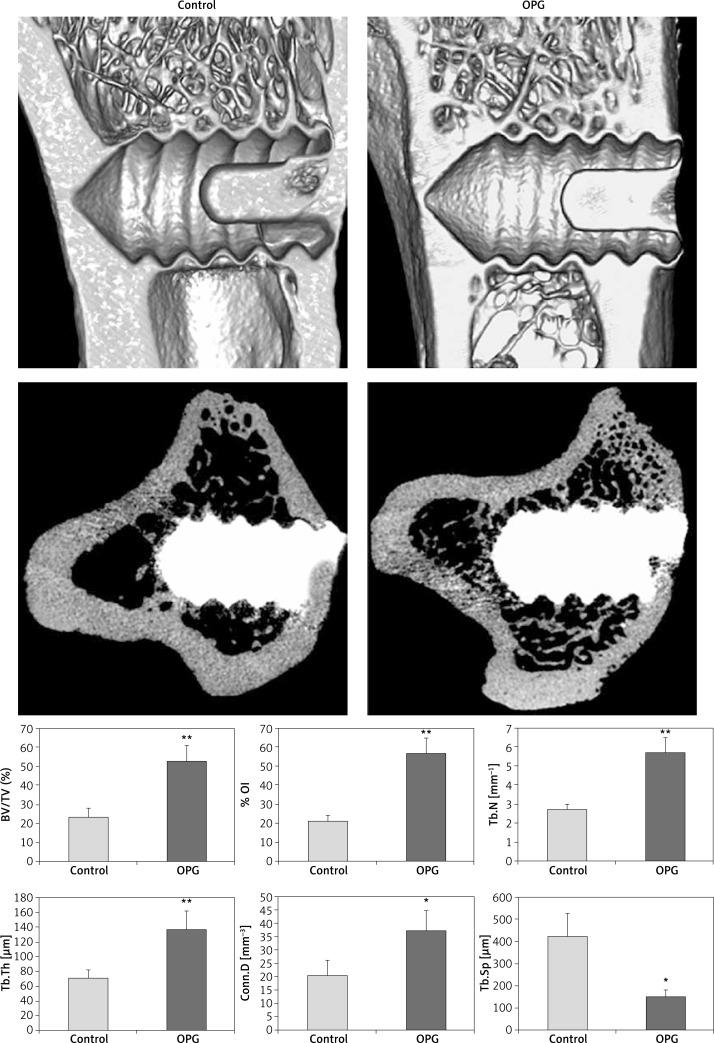

Twelve weeks after bilateral ovariectomy, each rat accepted two titanium screws in the proximal tibiae. All animals were then randomly divided into two groups: the control (10 rats) and OPG group (10 rats). Subcutaneous injection of OPG (10 mg/kg) or vehicle was performed three times a week. Eight weeks later, tibiae with screws were harvested for micro-computed tomography (μCT), histological and biomechanical analysis.

Compared to control, OPG increased the percent bone volume by 124%, the percent osseointegration by 167%, the mean trabecular number by 111%, the mean trabecular thickness by 92% ( < 0.01), the mean connective density by 95% ( < 0.05); and decreased the mean trabecular separation by 64% in μCT analysis ( < 0.05). Osteoprotegerin also increased bone area density by 160% and bone-to-implant contact by 234% in histomorphometric evaluation ( < 0.01), and increased the maximal push-out force by 228% in biomechanical test ( < 0.01).

Systemic administration of OPG improved implant osseointegration and fixation in ovariectomized rats, resulting from the increased peri-implant bone mass and improved trabecular microarchitecture.